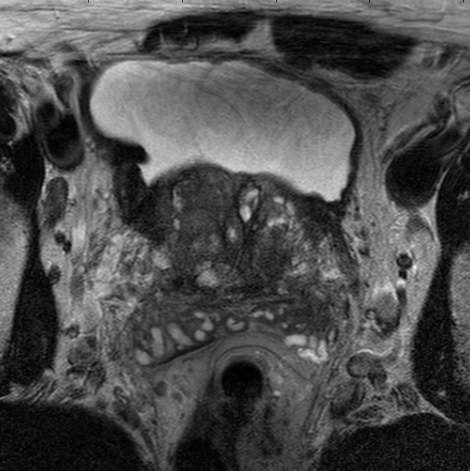

Our results seem to yield a solid evidence that imposing a deeply supervised method during training the network is a viable method for improving neural network’s performances for medical images segmentation. During training, all of these supervised layers will supervise the process of training and reduce the lose of prostate information. And due to the depth of the network’s large scale, the additional supervised layers can provide gradients information for early stage which resolves the problem of gradients diffusion. As shown in Fig 6 . It can be seen that the different supervised layers can detect different textures. The later layers are closer to ground truth and the early supervised layers possess more information. So the supervised layers located in early stages could provide the information which was lost during training for the later stage.